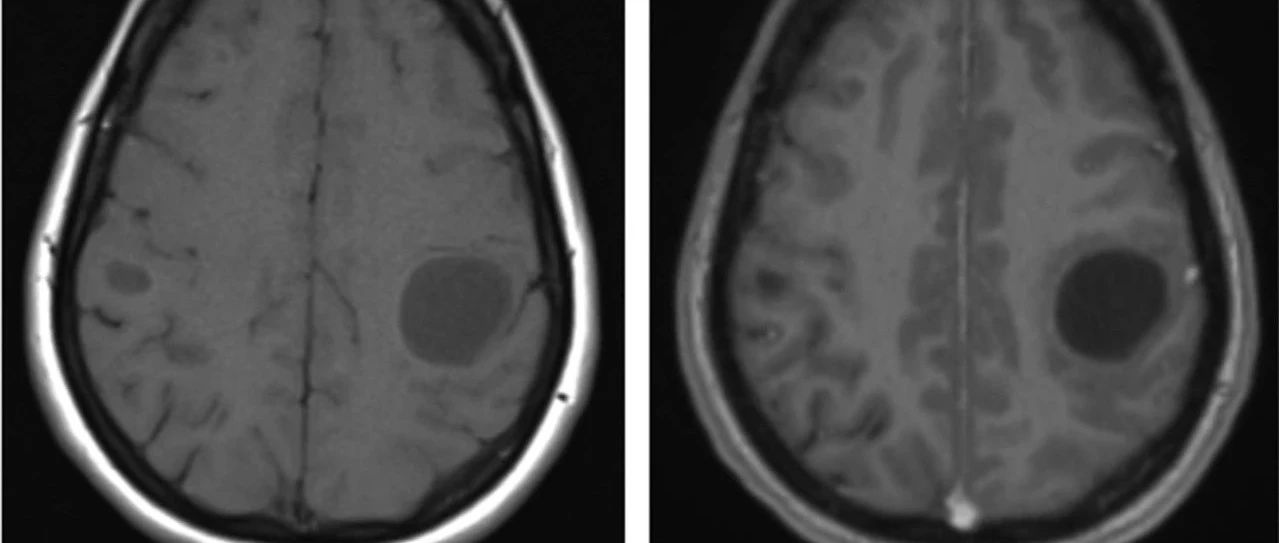

35岁女性,在2次右手局灶性感觉性发作后至医院就诊,其中第2次发展为全面性强直阵挛发作。查体未发现运动或感觉缺陷。MRI可见显示5个幕上病变,最大的2个为囊性病变——左侧中央后回上外侧30×30×32mm和右侧中央后回外侧7×9×6mm。所有病变均为T1低信号和T2高信号,周围有轻度血管源性水肿(图1A和C)。2个囊性病变呈周围强化、FLAIR高信号,且没有弥散限制(见图1B和D)。(图:MRI可见显示5个幕上病变,最大的2个为囊性病变——左侧中央后回上外侧30×30×32mm和右侧中央后回外侧7×9×6mm[A-D];病变呈T1低信号[A]和T2高信号,周围有轻度血管源性水肿[C];其在FLAIR上呈高信号[C],周围中度强化[B],无弥散受限[D];左侧中央后回上外侧病灶活检组织病理学显示脱髓鞘伴有囊性变和明显的星形胶质细胞增生[E],血管周围淋巴细胞成套[F],无残留髓鞘[G],CD163+巨噬细胞[H],以及大量反应性星形胶质细胞[I])...